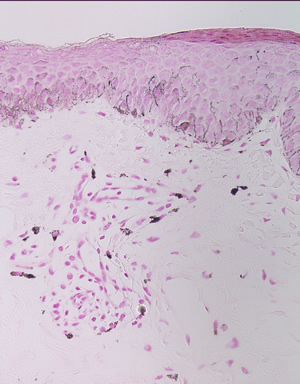

×40

×40-2

×100

×100-2

×200

×200-2